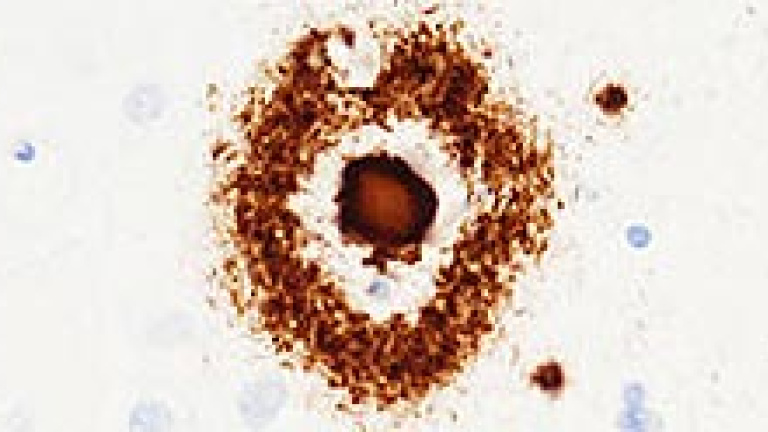

La revista Nature publica un trabajo que revela la relación del complejo proteínico NLRP3 con el alzhéimer. Esta molécula está implicada en fenómenos inflamatorios a través del llamado inflamasoma. En la enfermedad de Alzheimer, se ha visto que se da una activación crónica del inflamasoma y que NLRP3 podría estar bloqueando la eliminación del beta-amiloide, uno de los componentes patogénicos de la enfermedad y nocivo para las neuronas.

Los investigadores han trabajado con ratones transgénicos que desarrollan una patología similar al alzhéimer. En el modelo han observado que, cuando falta NLRP3, no se producen las alteraciones de memoria espacial, de comportamiento, de plasticidad sináptica y de densidad de espinas dendríticas en las neuronas piramidales del hipocampo de los animales transgénicos. Además, los animales sin la proteína tenían menos depósitos de beta-amiloide en el hipocampo y la corteza cerebral.

Los resultados indican que NRLP3 tiene una función fundamental en mecanismos inflamatorios del sistema nervioso central implicados en la disfunción conductual y cognitiva en la enfermedad de Alzheimer, así como un rol importante en la eliminación de las placas de amiloide.

También en muestras post mórtemLos científicos estudiaron también el cerebro post mórtem de personas que habían padecido alzhéimer, y obtuvieron resultados que apuntan en la misma dirección, relacionando la molécula NRLP3 con la inflamación observada en esta enfermedad.